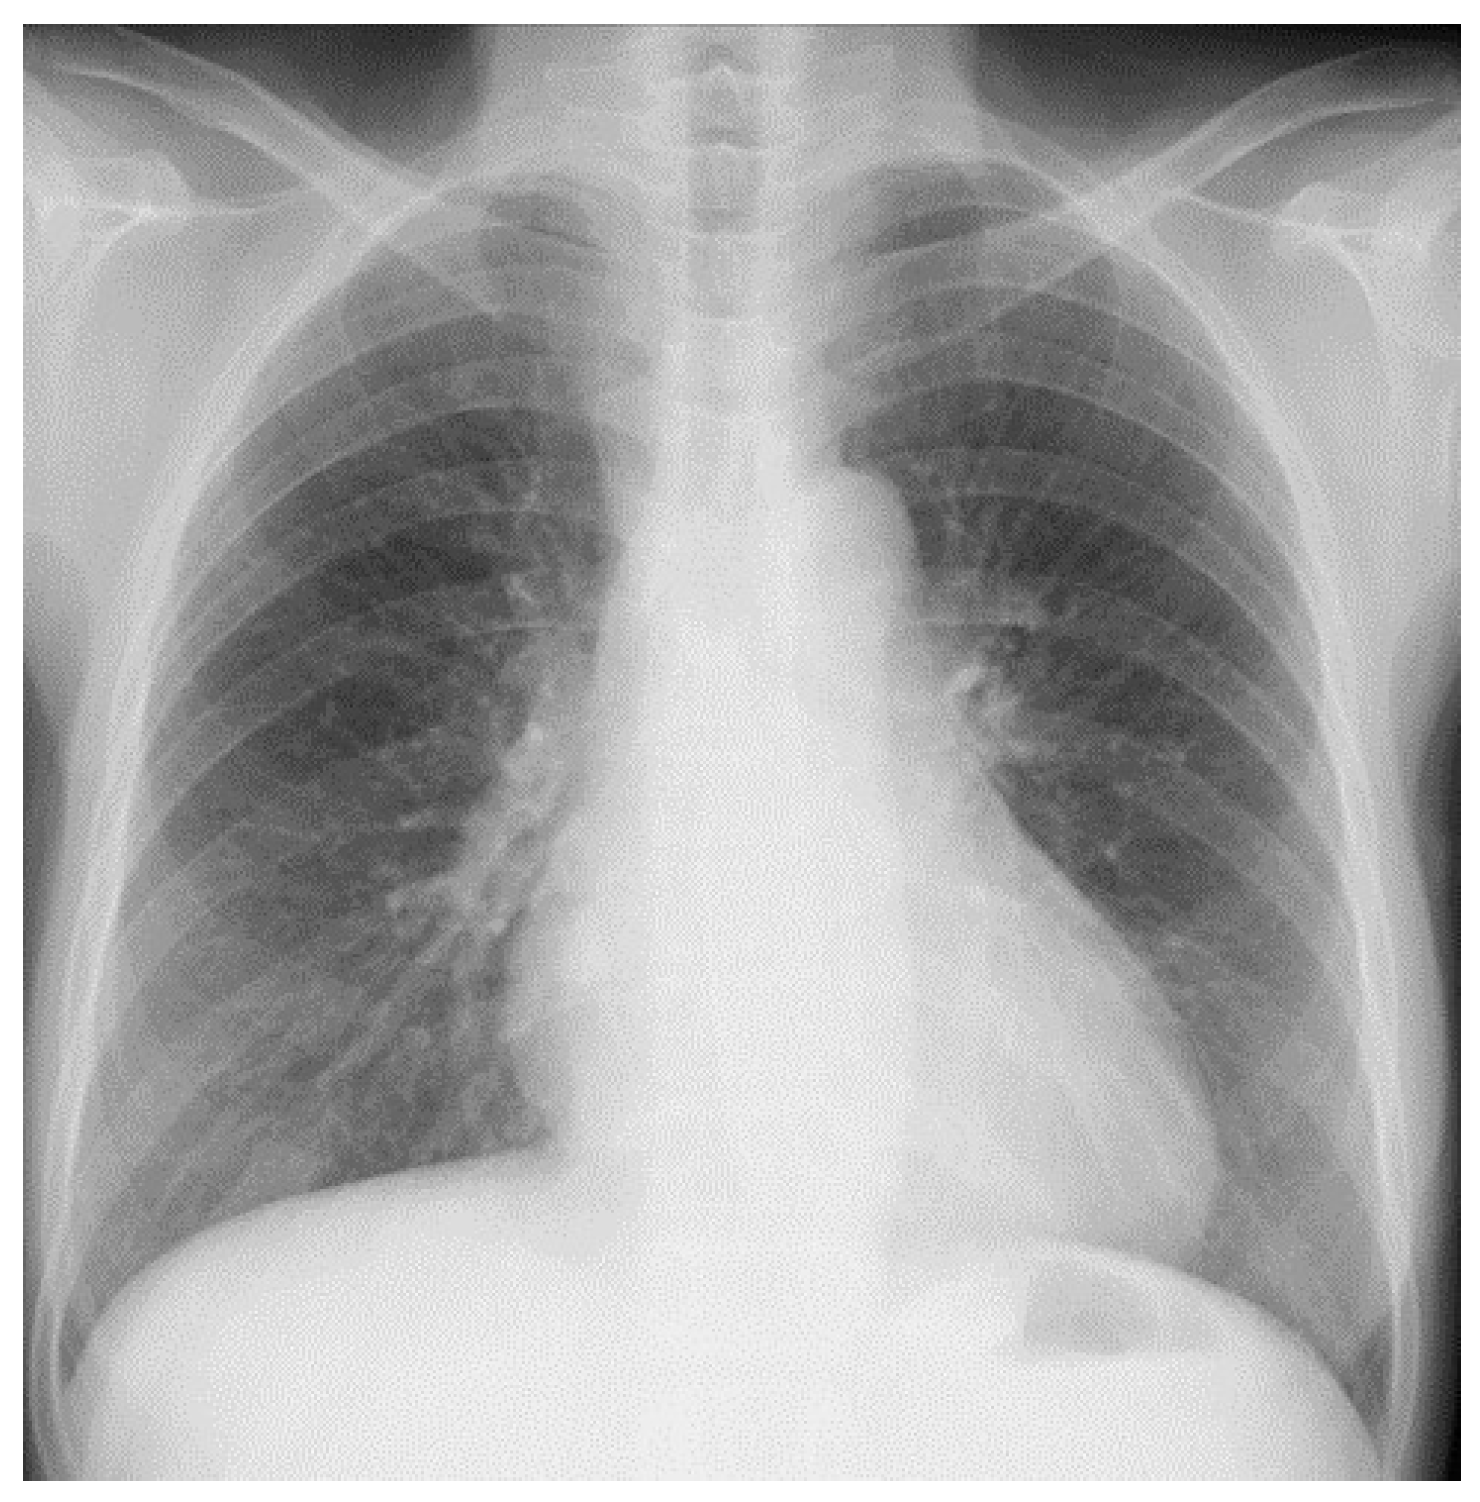

2. Case